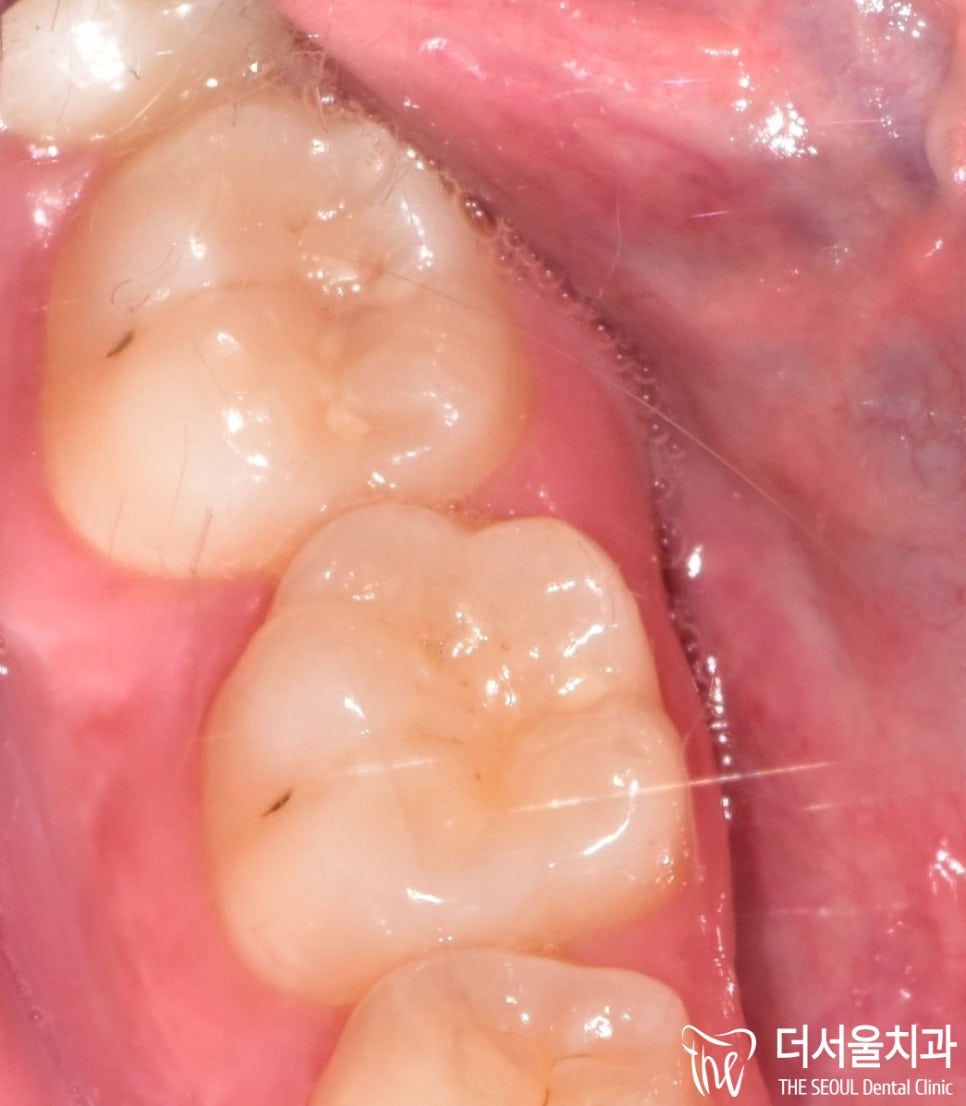

구강 속에서는 어떻게 나와있는지

확인한 결과…

저렇게 빼꼼 튀어나와있는데요.

아무래도 깊숙한 위치에다가

이를 뽑기 쉽지 않은 사랑니 발치 케이스로

꽤나 난항이 있을 것이라 예측되는데요.